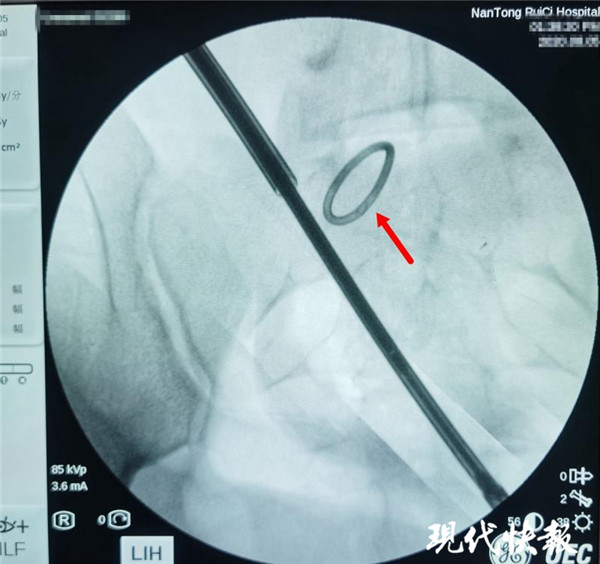

△術中X光,可清晰看到節(jié)育環(huán)

通過反復的X光定位,醫(yī)生終于發(fā)現(xiàn)了節(jié)育環(huán)的蹤跡,這枚“O”型節(jié)育環(huán)已經跑到了乙狀結腸中段右側系膜內,并且穿透了乙狀結腸右側壁肌層,貫穿腸腔。醫(yī)生分離切開腸系膜后,看見有近一半的節(jié)育環(huán)嵌頓在腸腔內。之后胡偉和吳忠新相互配合,將節(jié)育環(huán)完整取出,并根據(jù)術中談話時患者家屬選擇的手術方案,對腸壁的兩處瘺孔進行了修補縫合,手術順利結束。